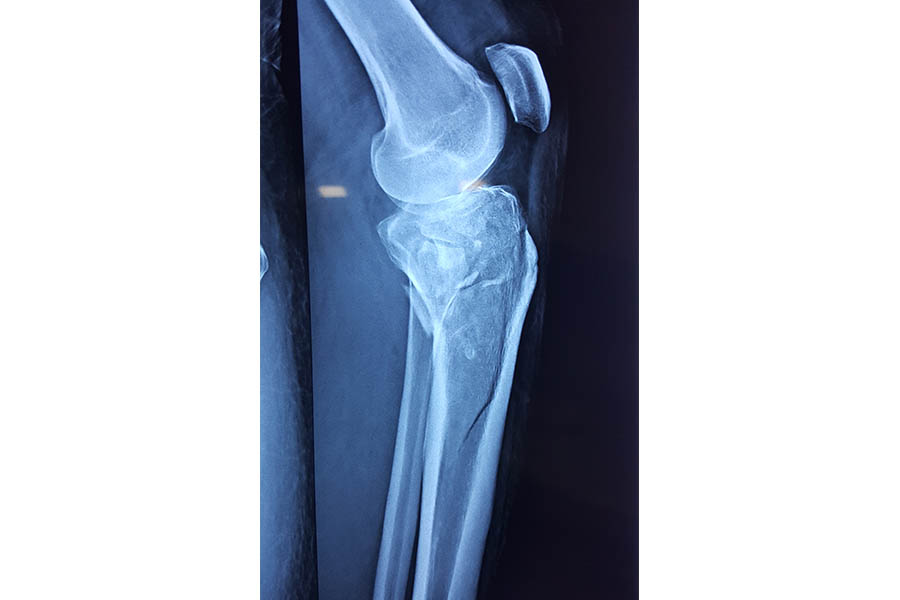

Trauma